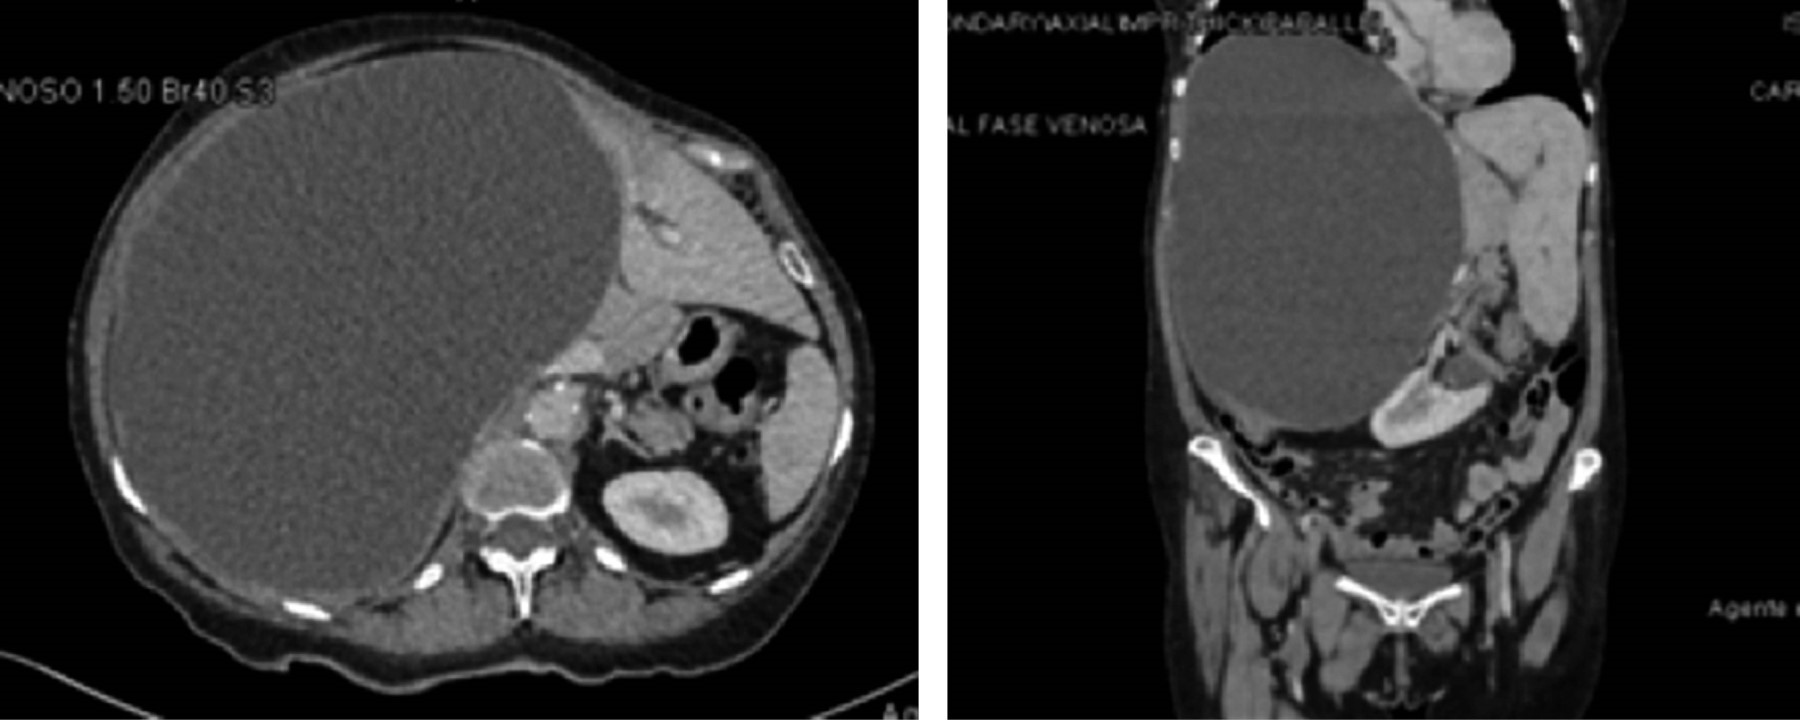

Pruebas de coagulación: tiempo de protrombina (TP) 12.8 segundos, índice internacional normalizado (INR) 1.17, tiempo parcial de tromboplastina (TPT) 27.2 segundos. Ultrasonido hepático reporta una masa ovoidea de contenido anecoico, no vascularizado, con volumen aproximado de 6,231.9 mL. Debido al gran volumen detectado, se decide realizar una tomografía axial computarizada (TAC) abdominal con contraste, con el fin de evaluar extensión y caracterización del quiste para una planificación quirúrgica. La TAC muestra una lesión dependiente de lóbulo derecho de 194.27 × 185.72 mm, con un volumen aproximado de 6,000 mL (Figura 1).

Figura 1